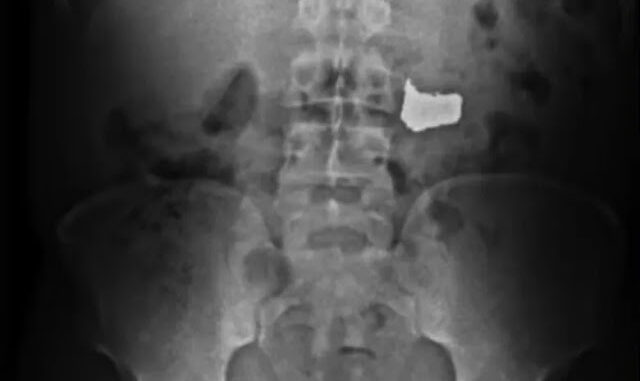

Segundo o órgão, antes de ser detido, na frente dos militares, o homem engoliu a corrente para tentar escapar da prisão. Ele foi levado, inicialmente, para a Unidade de Pronto Atendimento (UPA) dos Barris, onde passou por exames. Através de raio-x, foi atestada a presença da corrente no organismo do suspeito, que não teve nome divulgado.